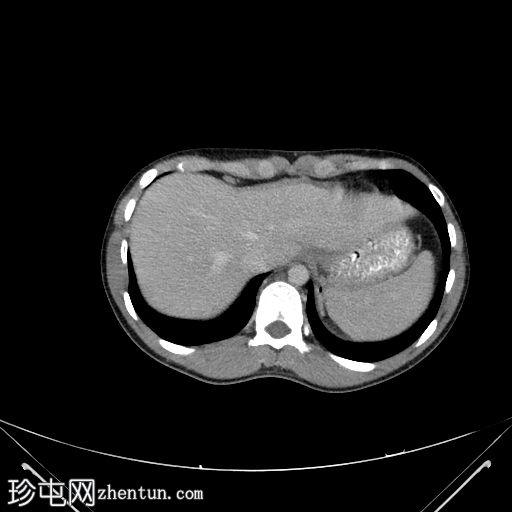

轴位增强扫描(门静脉期)

可见盲肠和末端回肠弥漫性环周肠壁增厚,导致严重的肠腔狭窄。可见多个区域淋巴结肿大,最大者大小为2.4 x 2.2 cm,伴中央坏死。

右侧结肠旁沟可见少量游离液体和脂肪条索影,盆腔内可见少量游离液体。